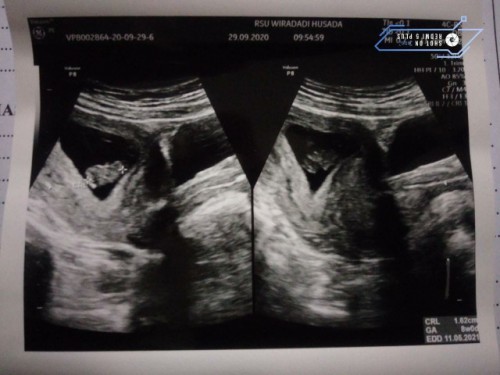

jumat kmrin usia khmilan aku 11+6 minggu, aq usg di rs. hasil usg bb & pjng bayiku sesuai sma umur khamilan. tpii kta dokter pertumbuhan mulut bayiku blm terbntuk seharusnya di usia khmilan sgtu sdh terbntuk kta dokter . aq sedih bgt dapet kbr bgtu, trus aq ngis 😭 takut klo anak anak aku knpa knpa , mohon doanya ya bun semoga nnti ank aku normal sehat. #bantusharing